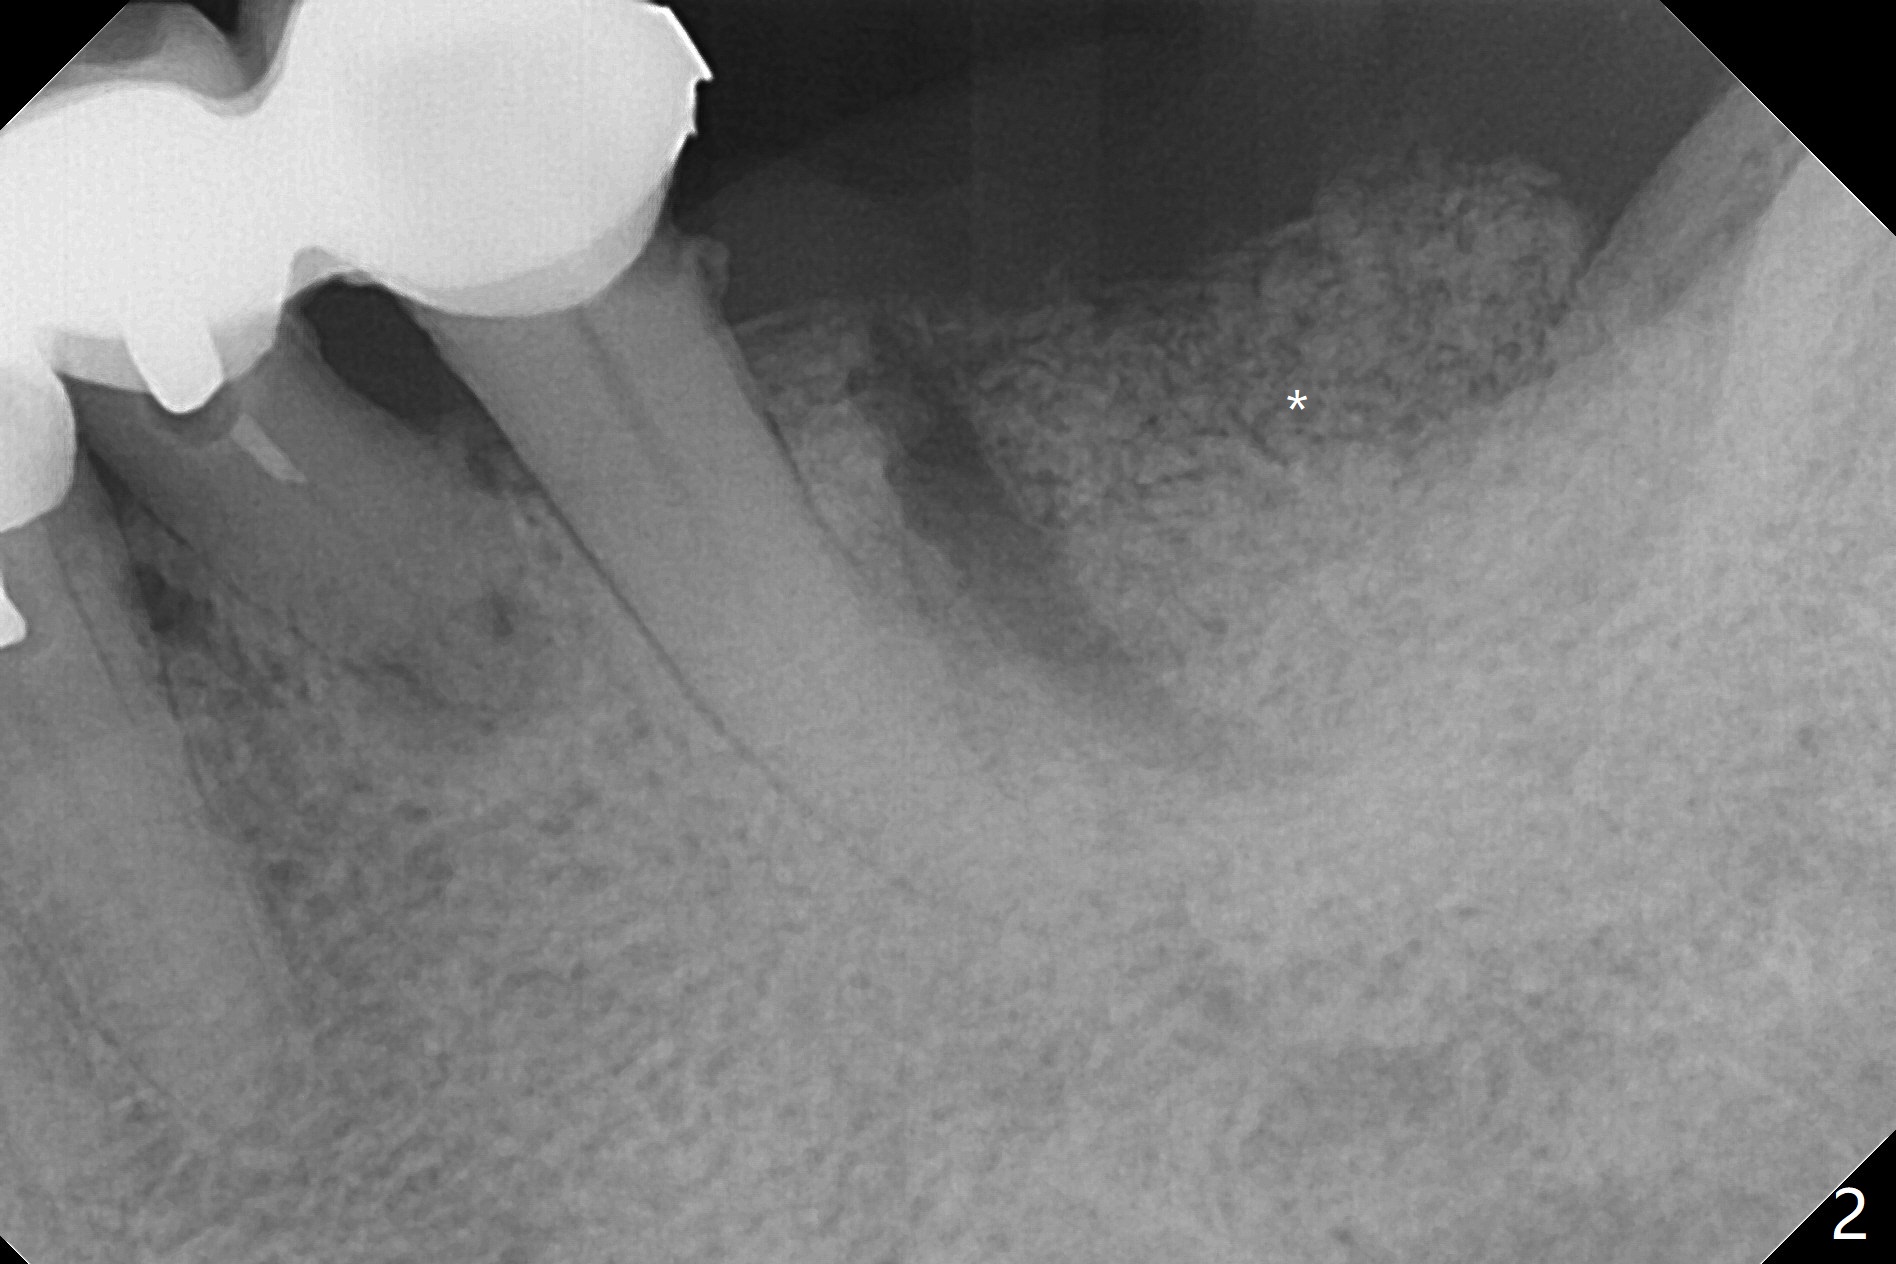

A 73-year-old woman cannot masticate on the left. It appears that the retainer at #19 breaks from a long-spanned FPD (Fig.1). After extraction and gross debridement, Vanilla graft is placed in spite of severe bone loss (Fig.2 *). She has returned once for follow up. The soft tissue heals. She has left the country.